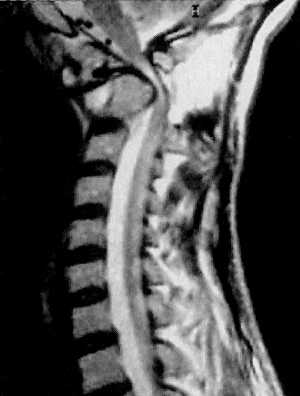

КТ и цифровая спондилография - важные методы диагностики вывихов атланта (рис.

1.7 и 1.8). МРТ позволяет определить не только дислокацию атланта, но и степень

компрессии спинного мозга (рис. 1.9).

|

Рис 1.7. Ротационный вывих атланта по

данным цифровой спондилографии |

Рис. 1.8. Вывих в атланто-аксиальном сочленении по данным

цифровой спондилографии |